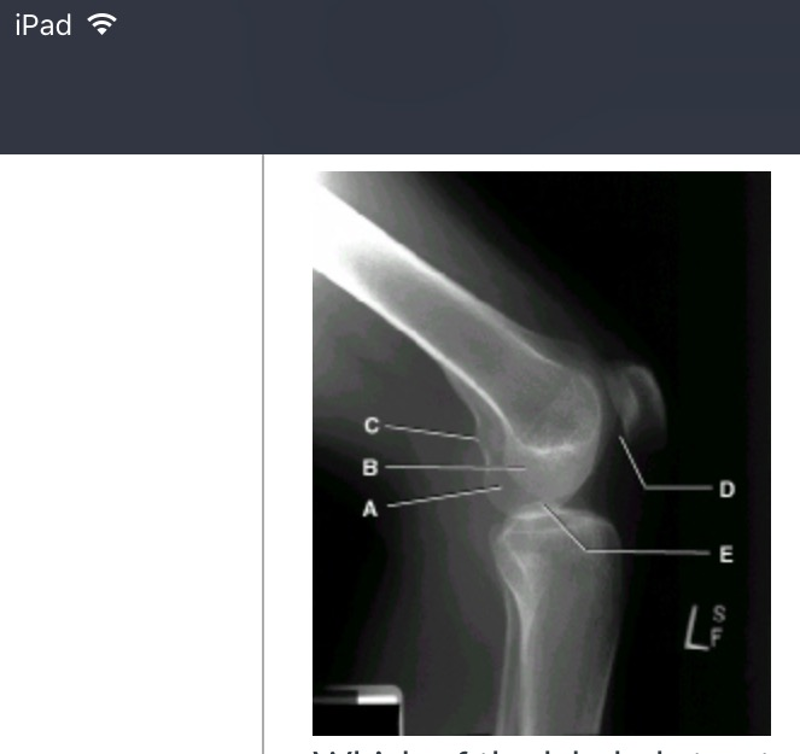

card image

which of the labeled structures is the adductor tubercle? (picture)

c